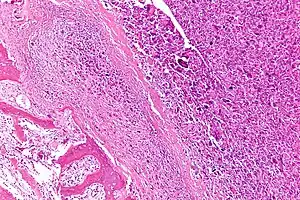

Intermediate-magnification micrograph of an osteosarcoma (center and right of image) adjacent to non-malignant bone (left-bottom of image): The top-right of the image has poorly differentiated tumor. Osteoid with a high density of malignant cells is seen between the non-malignant bone and poorly differentiated tumor (H&E stain).

Microscopically: The characteristic feature of osteosarcoma is presence of osteoid (bone formation) within the tumor. Tumor cells are very pleomorphic (anaplastic), some are giant, numerous atypical mitoses. These cells produce osteoid describing irregular trabeculae (amorphous, eosinophilic/pink) with or without central calcification (hematoxylinophilic/blue, granular)—tumor bone. Tumor cells are included in the osteoid matrix. Depending on the features of the tumor cells present (whether they resemble bone cells, cartilage cells, or fibroblast cells), the tumor can be subclassified. Osteosarcomas may exhibit multinucleated osteoclast-like giant cells.[21]